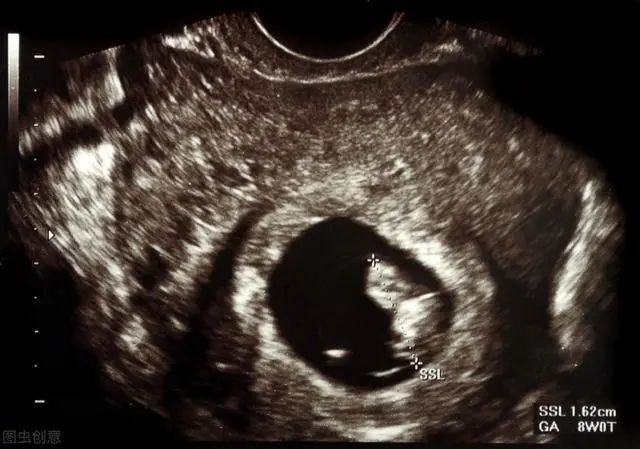

3、超声检查

B超或阴道彩超检查都是为了确定是否宫内孕,估算孕龄,排除宫外孕或其他疾病。平时月经规律,在停经35天时,超声下便可见到圆形或椭圆形妊娠囊;停经42天,可见到胚芽和原始心管搏动。当然,如果月经不规律或胚胎着床晚的话,那可要多推迟1周至2周再复查看看。